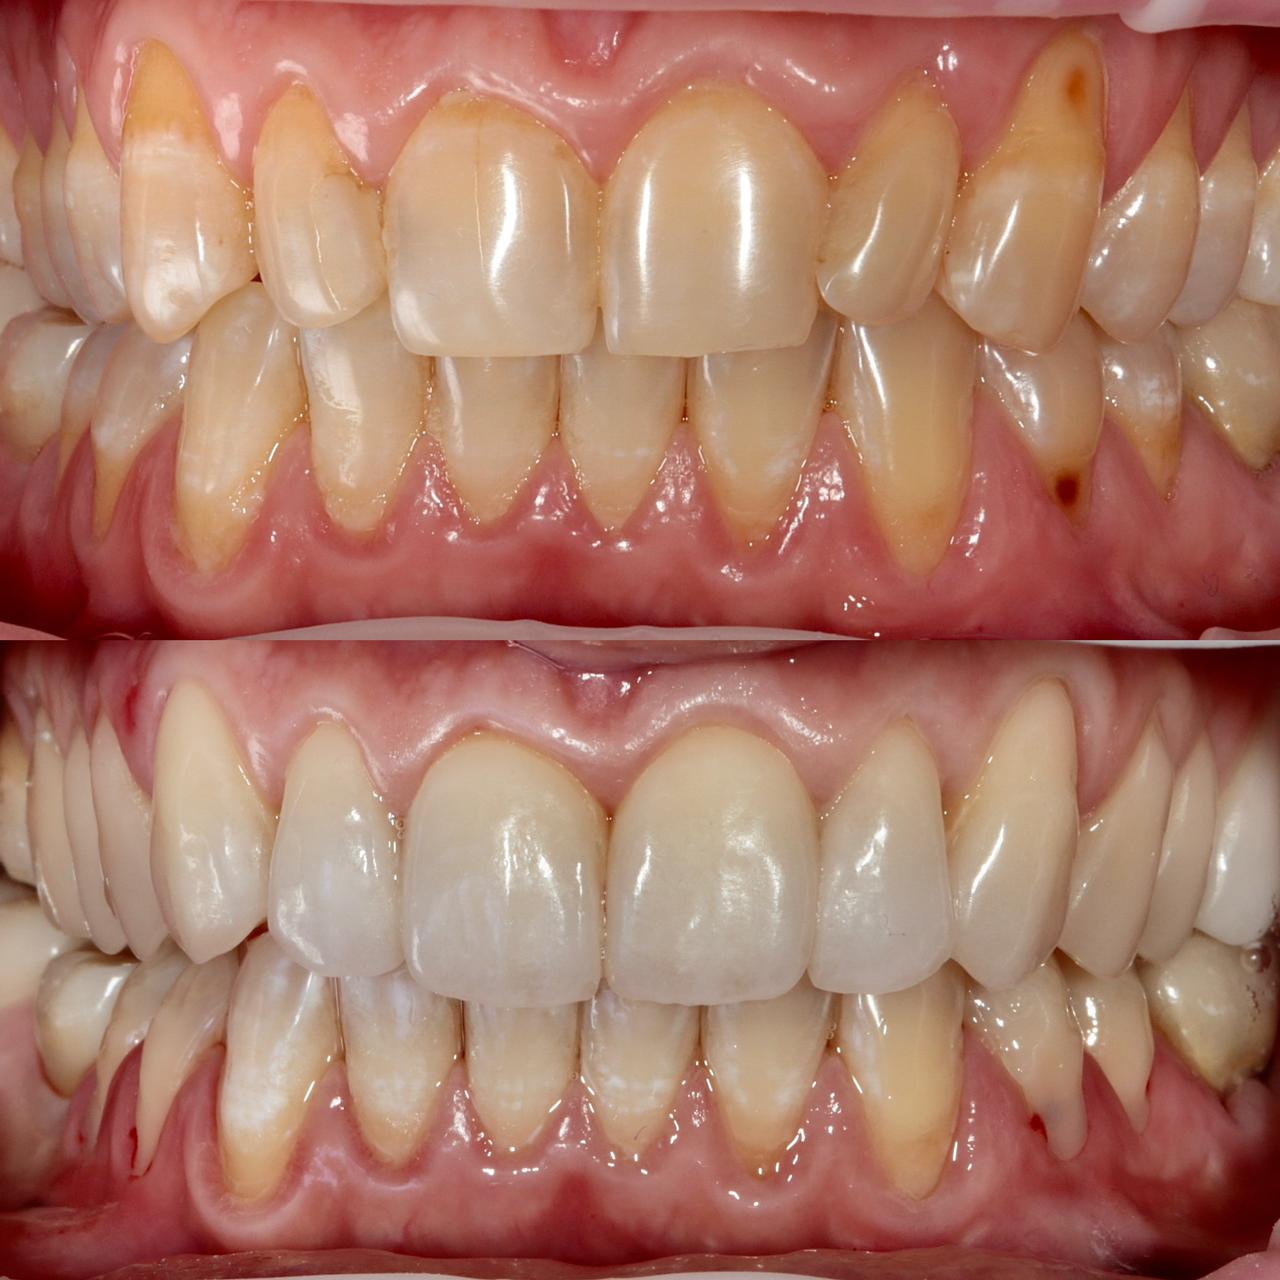

Примеры работ

Бережное и безболезненное лечение зубов